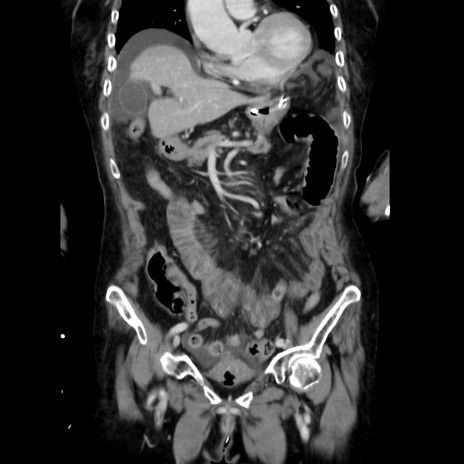

症例40(冠状断像)

【症例】90歳代女性

【主訴】腹痛・嘔吐

【現病歴】 食欲低下、嘔吐があり昨日他院受診。肺炎と診断され入院となる。入院後より腹部全体に圧痛あり。胃管留置され経過みていたが、症状持続するため、

当院転院となる。

【既往歴】胸椎圧迫骨折、胆石症

【身体所見】腹部:中央に激痛あり、圧痛あり、反跳痛不明

【データ】WBC 17100、CRP 18.82

冠状断像